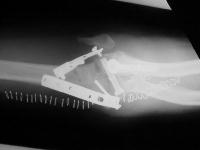

Clinical Example: Comminuted transcondylar distal humerus fracture

An example of a difficult management problem. This patient is a mid 60s year old woman who sustained multiple injuries in a motor vehicle accident, including bilateral calcaneal fractures and a closed distal humerus fracture. She was initially treated in another city.

Initial injury:

Films on arrival, one week after surgery. Neurovascular exam is normal. Early loss of fixation.